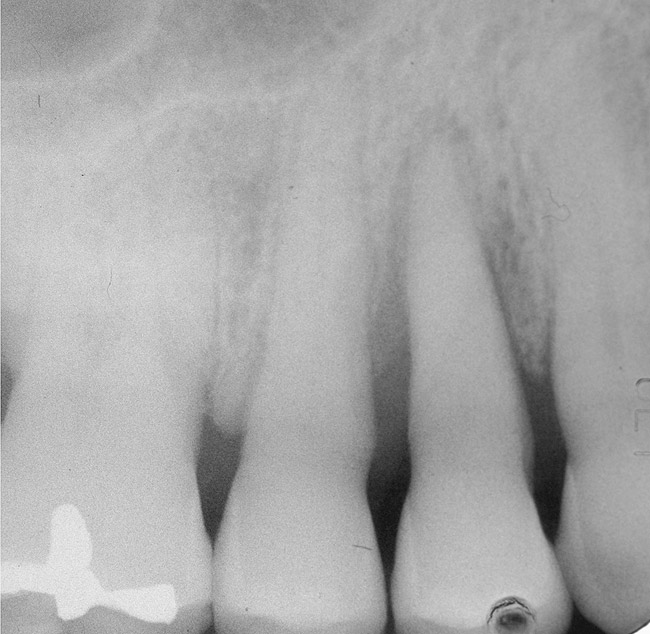

In treatment planning, the decay rate of the patient’s teeth, including the endodontic status of the individual tooth, becomes an important factor when considering long-term outcomes. In the pictured case (Figure 5), tooth No. 11, which previously had been treated endodontically, had recurrent decay and tooth No. 12 had advanced decay with endodontic involvement. In less than 30 days, recurrent decay that reaches the endodontic fill through a leaky restoration (temporary or not), ill-fitting crowns, or broken fillings can re-infect the entire length of the root canal system in a previously endodontically treated tooth.22 Therefore, saving a previously endodontically treated tooth, as in this case, may involve endodontic re-treatment, which can be a deciding factor for tooth preservation.

Figure 5  Recurrent decay of teeth Nos. 11 and 12. Note the proximity of the decay on both teeth to the osseous crest.

Figure 5